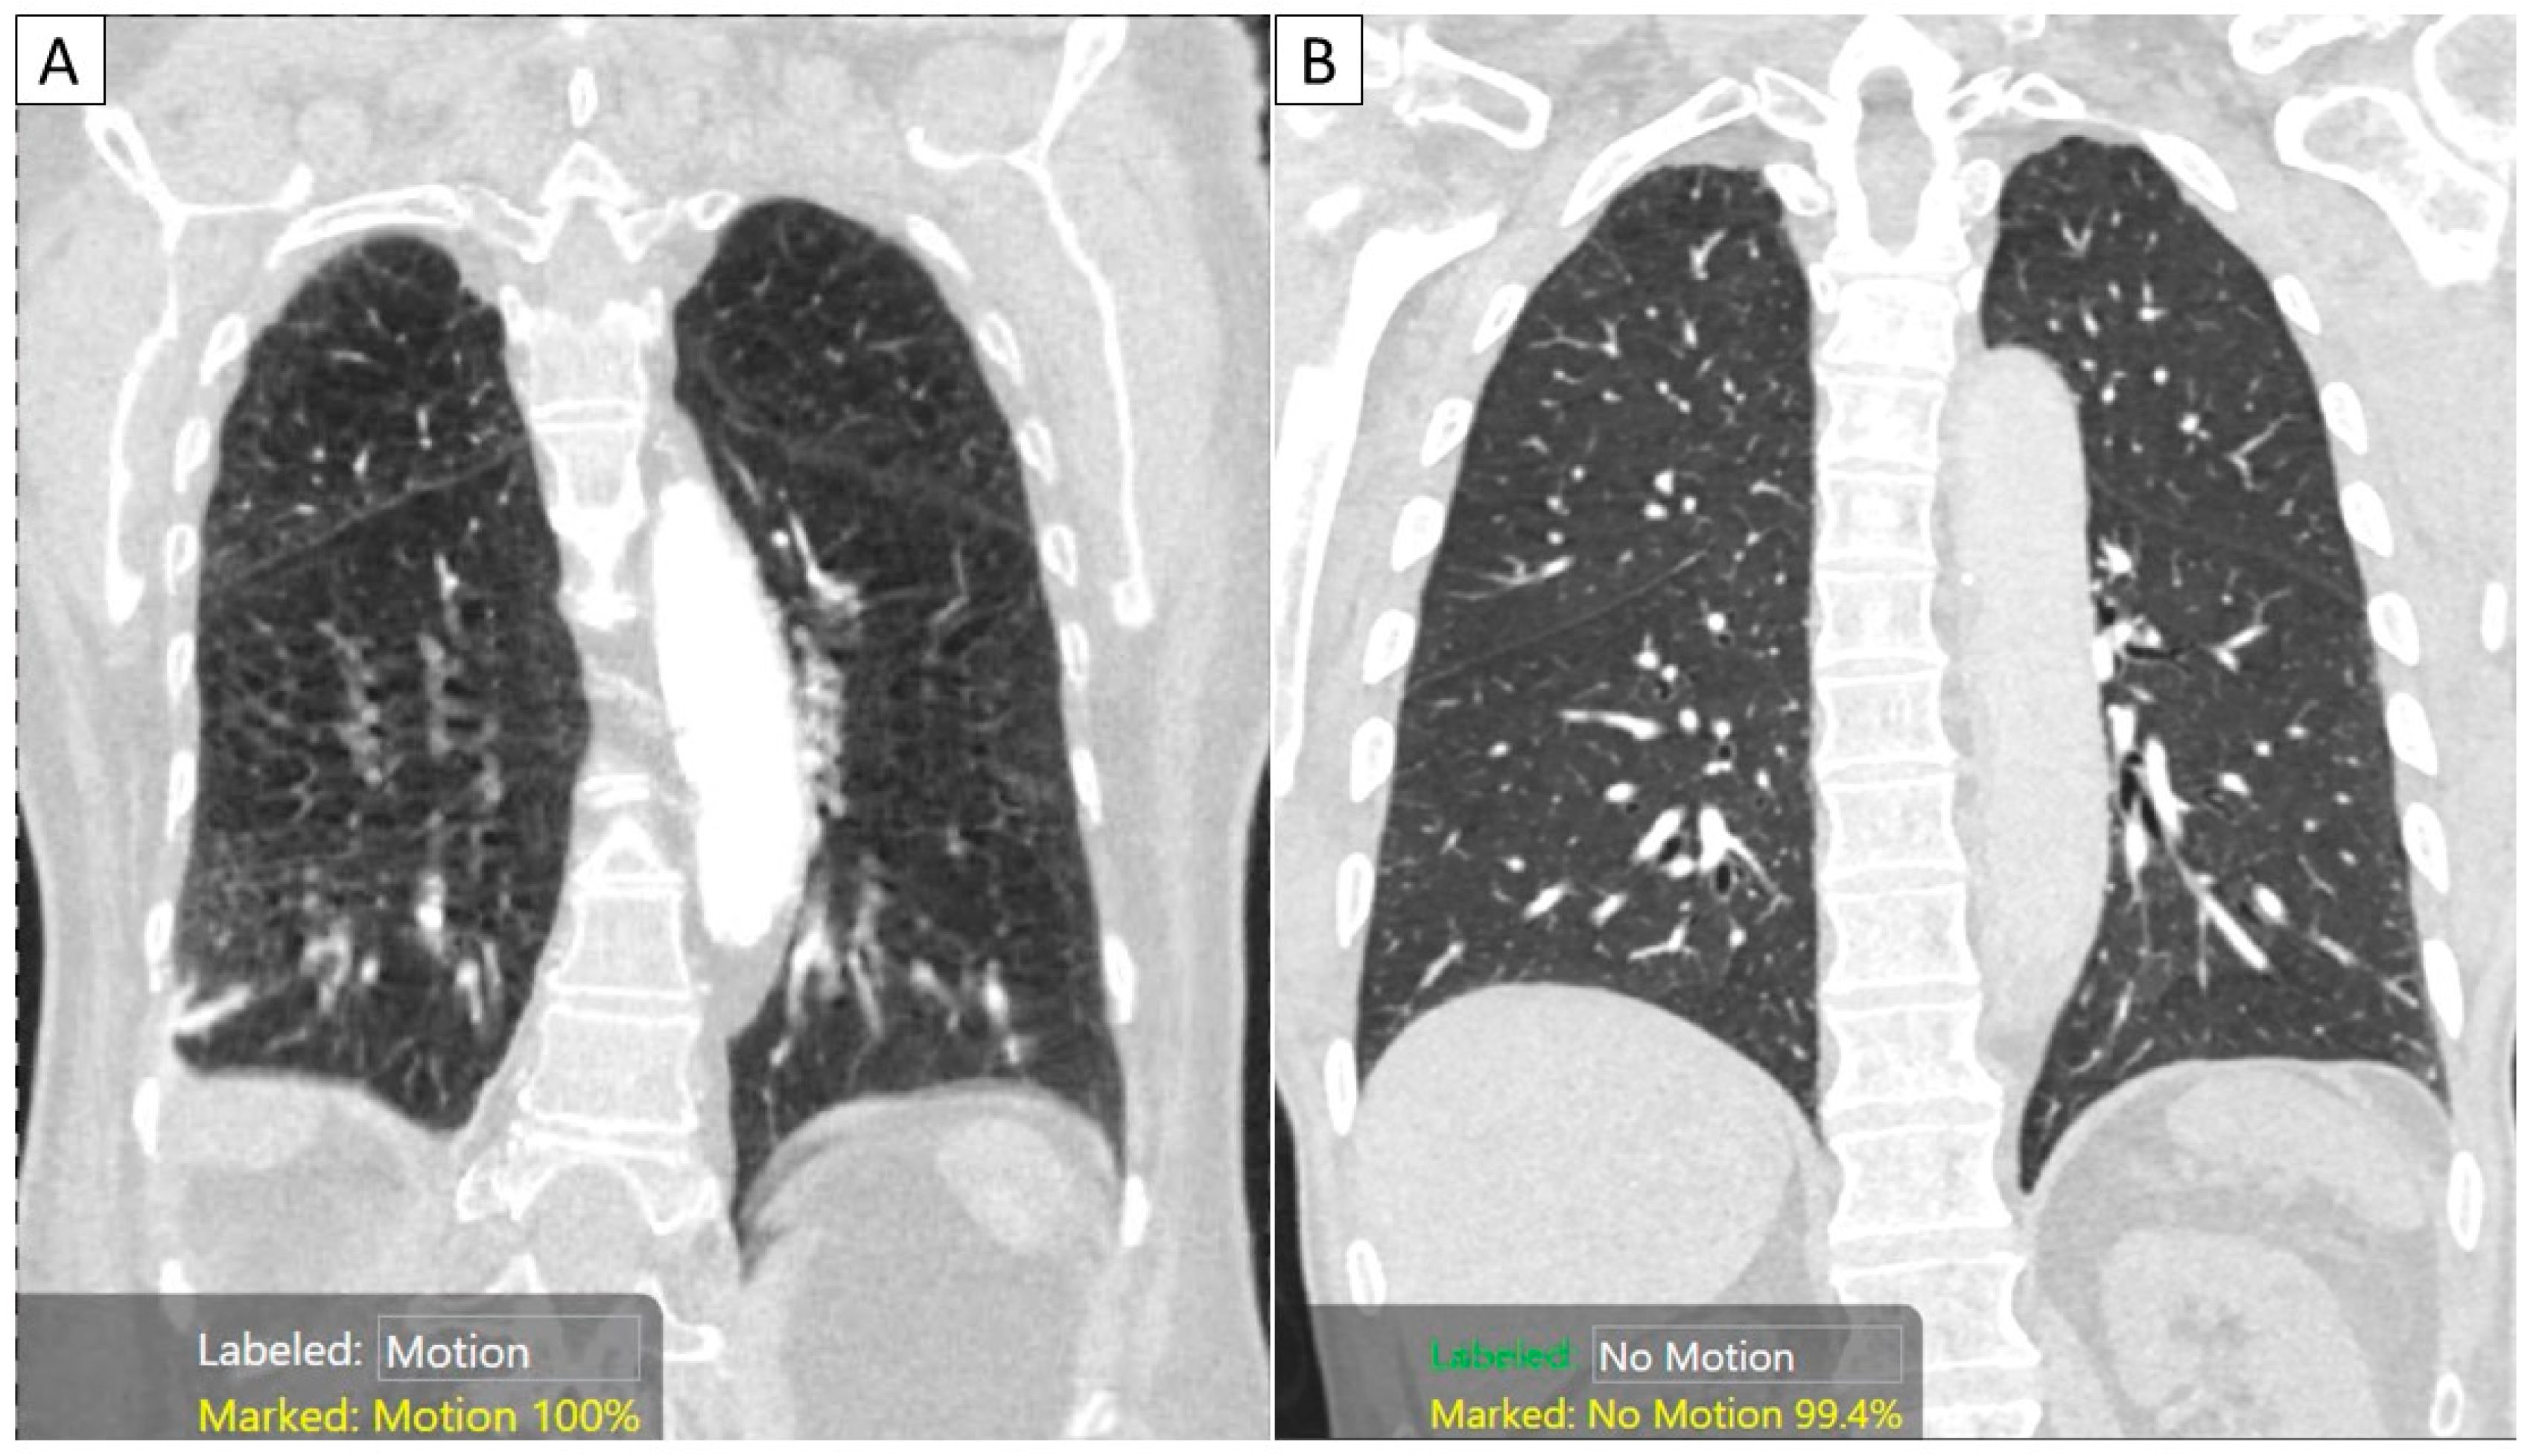

Figure 2. Coronal MPR images of CTPA examinations in two patients with (A) and without substantial motion artifacts. The AI algorithm correctly classified the images with motion ((A) with a 100% confidence score) and “no motion” ((B) with a 99.4% confidence score).